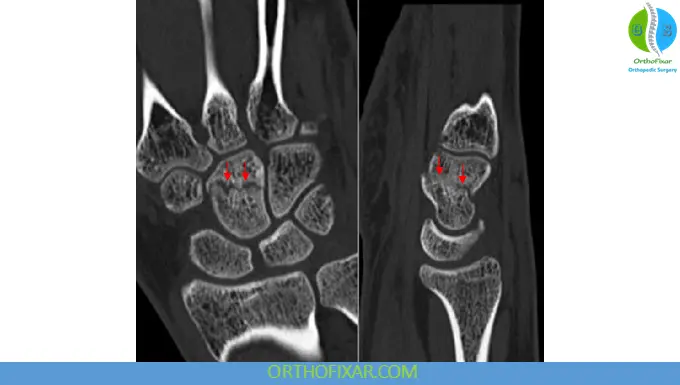

- Computed tomography (CT) for detailed assessment, especially when initial imaging is inconclusive

Advanced imaging is particularly important in detecting fragment displacement or rotational deformities.